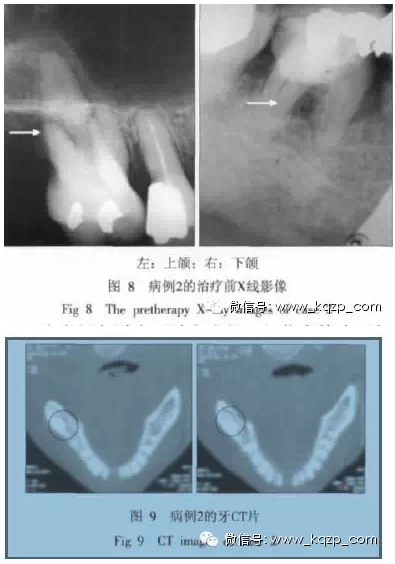

典型病例2,患者為女性,50歲。1個月來,每晚睡后1 h左右,右側(cè)牙齒出現(xiàn)陣發(fā)性疼痛,并向耳顳部放射??谇粰z查,17缺失,16和46、47有充填物,密合,未探及牙周袋,15已作根管治療;冷熱診反應(yīng)正常。X線牙片示:16遠(yuǎn)中根吸收至根尖(圖8左箭頭示);46、47根尖無明顯陰影,46根分叉陰影(圖8右箭頭示)。拔除16,46、47行根管治療后,癥狀仍未改善。請神經(jīng)科會診,未見異常。復(fù)查牙片,見46、47根尖近下齒槽神經(jīng)管處密度較高,拍攝上下頜全景片,見46、47根尖下方有一約3 cm×4 cm密度增高區(qū);拍攝牙CT片,可見密度增高影和下齒槽神經(jīng)管重疊(圖9中圓圈示)。做下齒槽神經(jīng)管減壓術(shù)后癥狀消失。

該病例主訴為牙髓炎癥狀,但臨床檢查無相關(guān)陽性體征。經(jīng)多個醫(yī)師反復(fù)會診、治療,癥狀均未減輕;通過加拍全景片和牙CT片才確定病因。該病例提示,對于牙痛病例,如對牙片有懷疑時,應(yīng)加拍上下頜全景片和牙CT片。